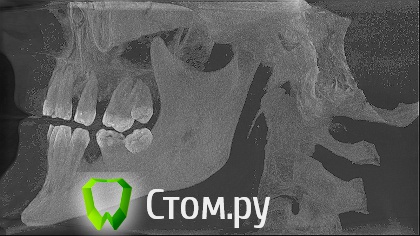

sergey765 Опубликовано 11 июня, 2014 Автор Поделиться Опубликовано 11 июня, 2014 посмотрите пожалуйста КТ. Ссылка на комментарий

sergey765 Опубликовано 11 июня, 2014 Автор Поделиться Опубликовано 11 июня, 2014 могу вам ещё снимков выложить.их довига. беспокаят меня боли после удаления .прошло 5 недель. снимки девушка лет 20 эти смотрела. сказала что у меня там инфекции дофига. типа давай я тебя на понедельник к хирургу запишу. он ранку вскроет. прочистит Ссылка на комментарий

Bier Опубликовано 11 июня, 2014 Поделиться Опубликовано 11 июня, 2014 это все не информативные кадры, в прикрепленных темах есть инструкция, выкладывайте КТ целиком, наш рентгенолог скачает и выложит срезы. 3 Ссылка на комментарий